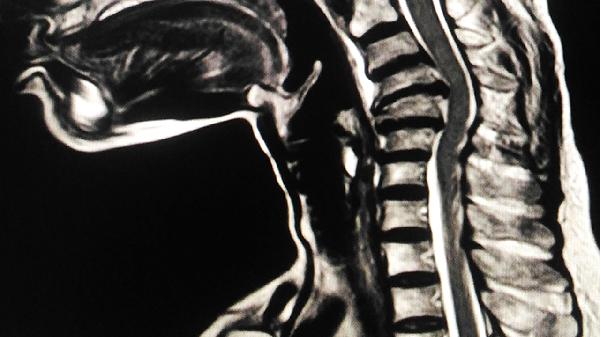

5、肝移植评估:

终末期肝病模型评分≥15分或反复肝性脑病发作患者需评估移植指征。移植后多数患者脊髓病变停止进展,但神经功能恢复需1-2年随访观察。